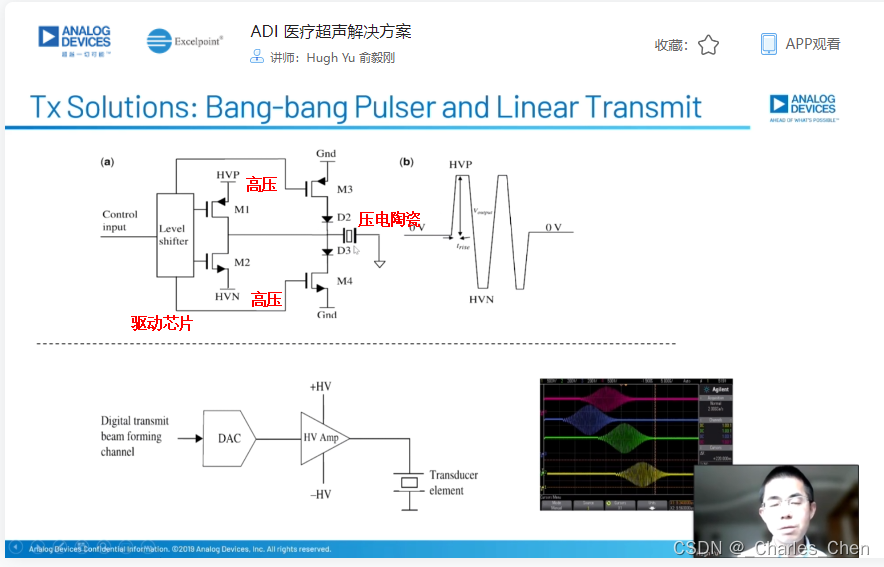

高压发射机

数字发射波束成形器用于产生所要求的数字发射信号,以正确的时间和相位生成聚焦发射信号。高性能超声系统可通过任意波形发生器产生复杂的发射波形,从而优化图像质量。这些情况下,发射波束成形器以大约40MHz速率生成8位至10位数字字符,并以此产生所要求的发射波形。数/模转换器(DAC)将数字波形转换成模拟信号,通过线性高压放大器进行放大,用于驱动传感器单元。由于这种发射技术占用较大体积,而且价格昂贵、需要消耗较高能量,所以,这种架构只限于昂贵的非便携设备。多数超声系统并不使用这种发射波束成形技术,而是采用多级高压脉冲发生器产生需要发射的信号。在这种替代方案中,利用高集成度、高压脉冲发生器快速切换传感器单元至适当的可编程高压电源,产生发射波形。为了产生一个简单的两极发射波形,脉冲发生器需要交替地将传感器单元切换到由数字波束成形器控制的正、负发射电压。更复杂的设计可以让传感器单元切换至多路电源和地,从而产生更复杂、性能更好的多重波形。

Tx/Rx开关

Tx/Rx开关可以保护低噪声放大器免受高压发射脉冲的影响,同时在接收间歇期间隔离低噪声放大器输入和发射机。该开关一般采用一组正确偏置的二极管阵列实现,当有高压发射脉冲出现时,它们会自动闭合或断开。Tx/Rx开关必须具备很快的恢复时间,以保证接收机在发射一个脉冲后能够立刻开启。这些快速恢复时间对于浅埋成像和提供低导通电阻确保接收灵敏度至关重要。